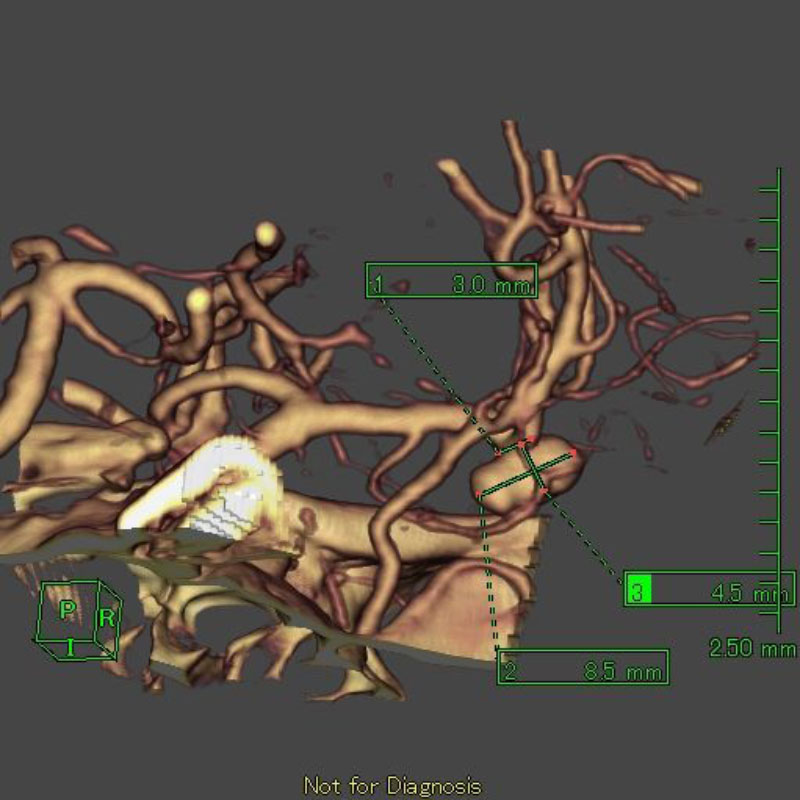

22

'26年5月

70代

右中大脳動脈瘤

クリッピング術

手術前

クリップ前

クリップ後